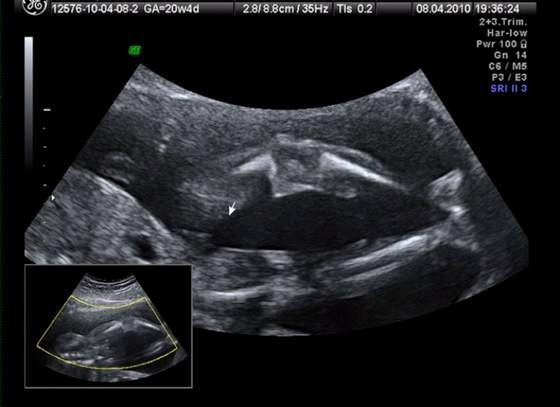

śliczna panienka rośnie :-)Przyszła kolej na moją śliczną córunię - mam nadzieję, że już jej nic nie wyrośnie, bo się przyzwyczaiłam... :-)

kolejno: uśmiech, pipulka, twarzyczka i krągła dupcia